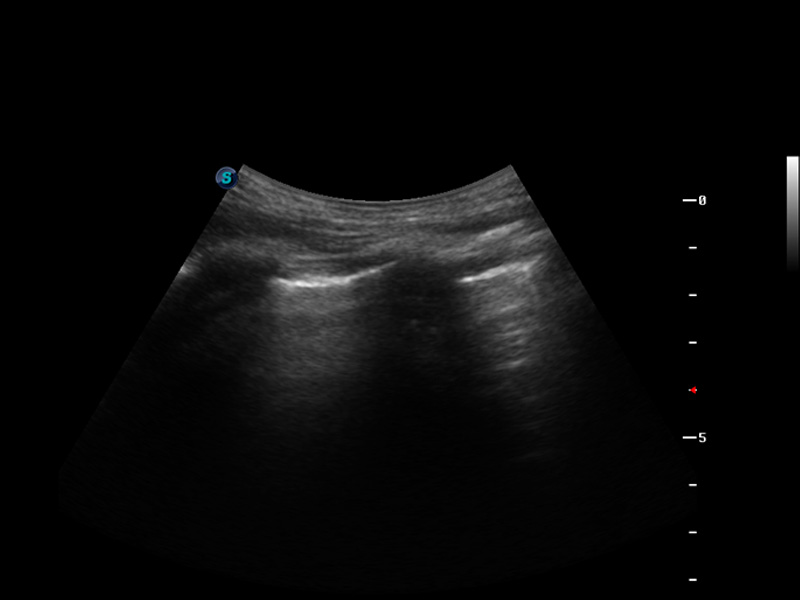

S9便携式彩色多普勒超声诊断仪是美狮贵宾会官网研发的高端便携彩超设备,外观设计新颖、产品性能卓越。S9在便携超声领域采用了突破传统的触摸屏交互设计,并以先进的软件硬件技术和设计理念,为您带来清晰的图像质量、稳定的工作性能和便捷的操作体验。

μ-Scan微米成像